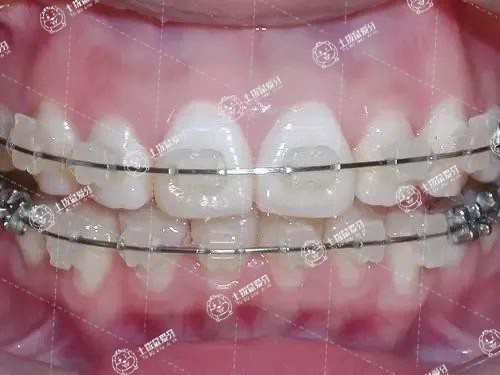

牙齒擁擠矯正需要的價(jià)錢(qián)一般是10000-80000元左右,這個(gè)價(jià)錢(qián)要根據(jù)選擇的矯正方式來(lái)看。矯正牙齒擁擠的方式有傳統(tǒng)鋼絲矯正以及隱形矯正和美容冠矯正等,選擇不同的矯正方式,操作難度不同,做出來(lái)的效果也不一樣,所以?xún)r(jià)錢(qián)上會(huì)有差別。如果選擇隱形牙套進(jìn)行牙齒矯正,那么價(jià)格就略貴,大概在80000元左右,如果選擇傳統(tǒng)的鋼絲牙套進(jìn)行牙齒矯正,價(jià)格就要便宜一些,大概在10000元左右。矯正后要注意口腔衛(wèi)生,禁止食用堅(jiān)硬的食物,例如硬殼、骨類(lèi)食品,飯后要漱口。

牙列擁擠的矯治步驟和大多數(shù)錯(cuò)(牙合)畸形的矯治步驟是一樣的,主要包括前期的準(zhǔn)備過(guò)程。要先檢查口內(nèi)情況,并拍攝相應(yīng)X光片,了解牙齒在骨頭里的情況以及上下頜骨的情況,然后進(jìn)行取模、拍照。

收集好資料以后醫(yī)生會(huì)進(jìn)行分析,得出相應(yīng)的治療方案,與患者仔細(xì)交流,獲得同意后就會(huì)開(kāi)始下一步的治療計(jì)劃。如果需要拔牙,會(huì)建議患者去拔牙,如果不需要拔牙,可能建議可以開(kāi)始戴牙套,戴完牙套以后一般1個(gè)月復(fù)診1次即可,總的治療時(shí)間大概為2年半,最后是拆牙套。